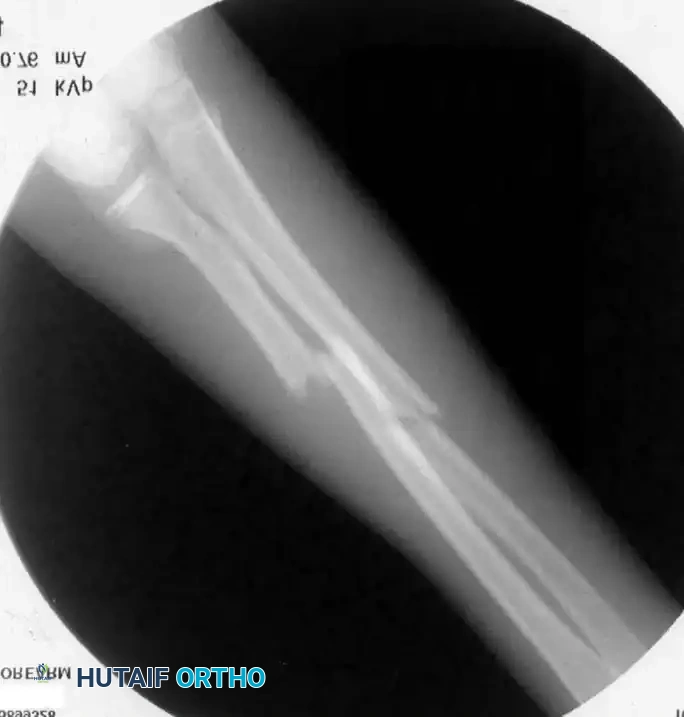

Image

Indications for Operative Treatment

According to Weber et al. and Nielson and Simonsen, operative treatment for middle-third fractures is indicated in the following scenarios:

1. Open fractures requiring surgical débridement.

2. Older children (approaching skeletal maturity) where remodeling potential is exhausted. Fuller and McCullough noted that gross malunion does not correct in girls older than 8 years or boys older than 10 years.

3. Irreducible fractures due to soft-tissue interposition.

4. Multiple refractures occurring within a short timeframe.

5. Failed closed reduction after multiple attempts.